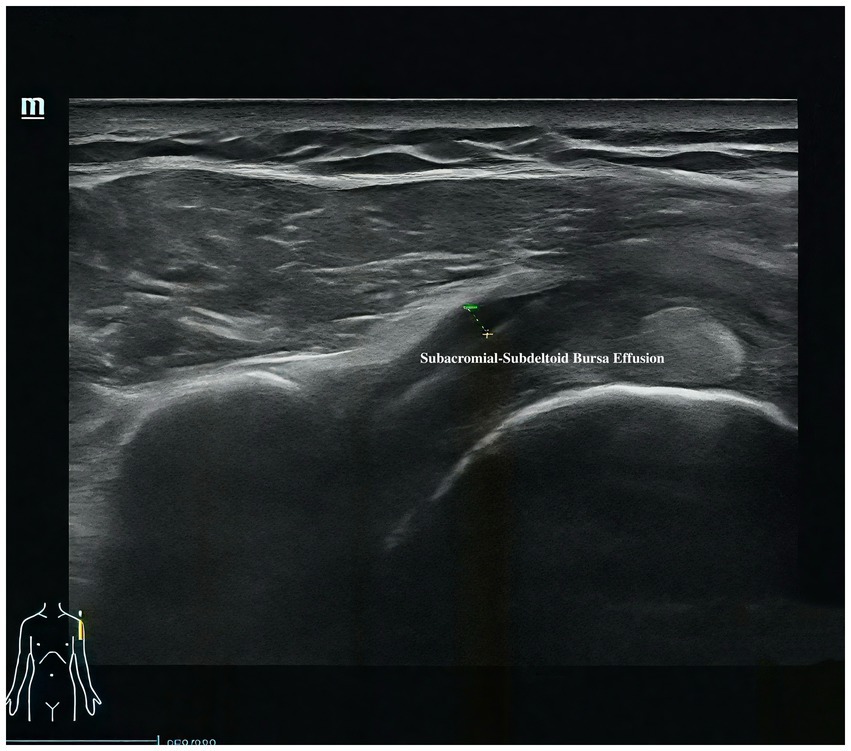

Musculoskeletal ultrasound is a practical and noninvasive method for detecting structural abnormalities commonly associated with PSSP. Key indicators include the distance from the acromion to the greater tuberosity of the humerus (Figure 9), effusion around the long head of the biceps tendon sheath (Figure 10), calcification in the supraspinatus (Figure 11) and subscapularis tendons, and increased thickness of the subdeltoid bursa (Figure 12). Effusion around the biceps tendon sheath often reflects inflammation or tendinopathy, which can contribute to pain and limited mobility. Calcifications in the supraspinatus and subscapularis tendons are typically associated with chronic rotator cuff conditions that result in impingement and reduced range of motion. Thickening of the subdeltoid bursa is suggestive of bursitis, a frequent source of discomfort in PSSP patients (21).

Figure 12

Ultrasound image showing a subacromial-subdeltoid bursa effusion. The labeled area highlights fluid accumulation in the shoulder region, depicted as a dark area beneath the muscles. A small diagram in the lower left shows the shoulder's anatomical location.

Figure 12. Thickness of the subdeltoid bursa.